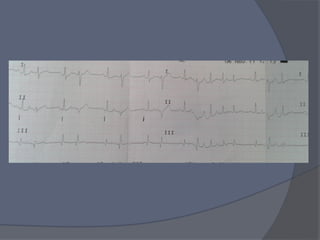

   La paciente se torna con disnea y a la

auscultacion cardiaca la encuentran

arritmica.

Pa: 120/70 FR 28 Sat 97% FC 80 x min

TOMAN ECG

La paciente se torna con disnea y a la auscultacion cardiaca la encuentran arritmica. Pa: 120/70 FR 28 Sat 97% FC 80 x min TOMAN ECG